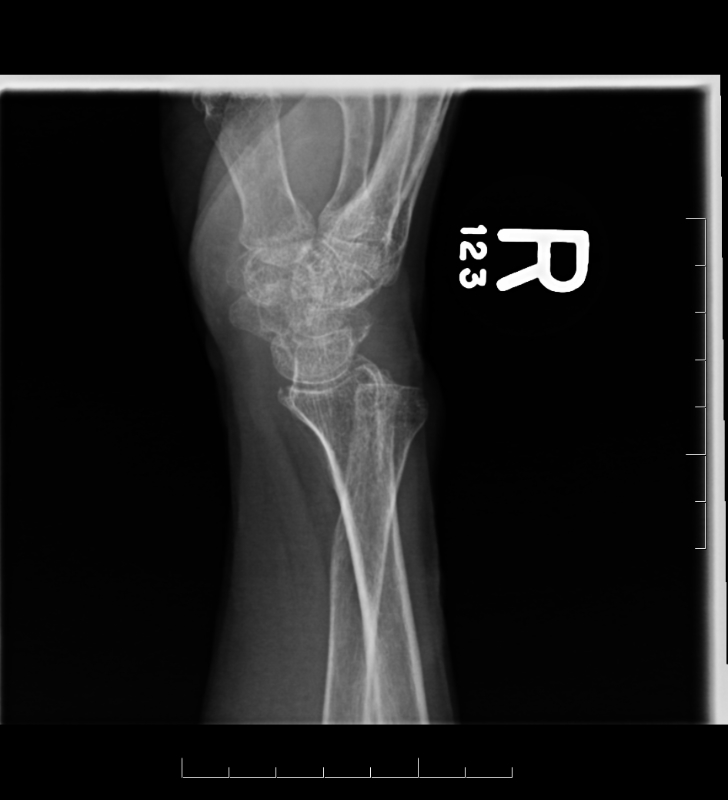

Posttraumatic DRUJ Arthritis Musculoskeletal Key

DRUJ Instability The Bone School

DRUJ Injury A Common Problem in Sporting Individuals Sport Doctor London